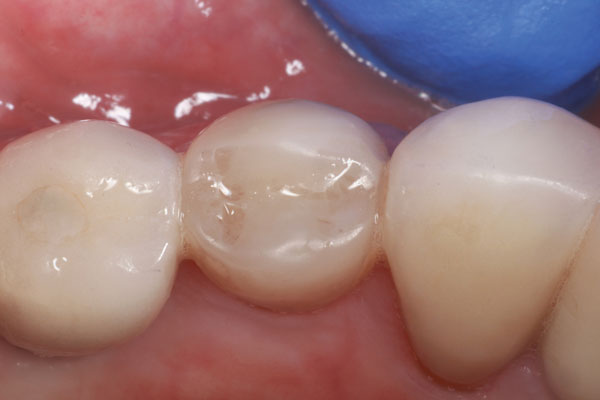

Un cemento de resina de curado dual / material de acumulación (Core-Flo DC Lite, BISCO) se mezcló y se colocó primero en el poste y la manga. A continuación, se colocó una pequeña cantidad de cemento en el canal y se insertaron rápidamente el poste y el manguito. El poste se empujó firmemente hacia abajo en el canal y se sujetó mientras se empujaba la manga hacia abajo con un par de pinzas de algodón. Luego se colocó resina adicional para rellenar y acumular hasta el nivel deseado, y se mantuvo una luz de curado sobre el aspecto oclusal durante 40 segundos (Figura 6). Después de que el área se aisló de la humedad y se dejó fraguar por completo durante 3 minutos, se tomó una radiografía del poste y el manguito con la acumulación (Figura 7), se realizó una preparación de la corona (Figura 8) y se fabricó un provisional para el paciente (Figura 9). Regresó 3 semanas después para que se asentara la corona final (Figura 10).

Imagen 6 Vista bucal del poste adherido y el manguito y la acumulación de muñón.